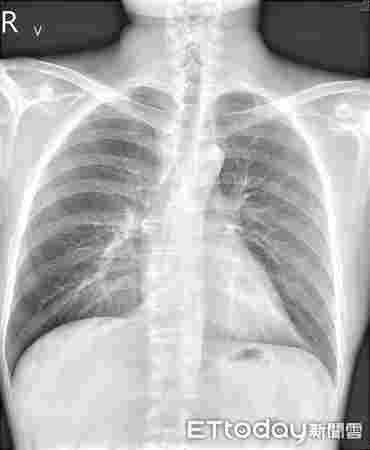

在短短幾個月的時間里,該男子開始出現咳嗽、氣喘、痰多、呼吸困難等呼吸道癥狀,以及全身皮膚干燥瘙癢的嚴重過敏反應。 他最近因懷疑電子香煙引起過敏反應而住進臺北一家醫院。

但皮膚病只是問題的一部分,這位臺灣醫生補充說,他的病人還患有哮喘,被診斷為肺炎,他的血液檢查也顯示他的過敏指數飆升。 聽他這么說,都是因為那些討厭的電子煙。